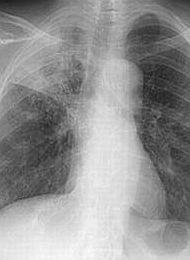

La tuberculosis (TBC) es una enfermedad infectocontagiosa, prevenible y curable, causada por una micobacteria denominada Mycobacterium tuberculosis, que también es conocida como Bacilo de Koch y se transmite a través del aire. Esta bacteria puede atacar cualquier parte del cuerpo como el cerebro, la columna vertebral, entre otros; sin embargo, la enfermedad generalmente afecta a los pulmones. Presenta síntomas como os persistente por dos semanas o más; fiebre; tos con flema que puede estar acompañada de expulsión de sangre; pérdida de apetito; sudor durante la noche; dolor de pecho; debilidad y cansancio